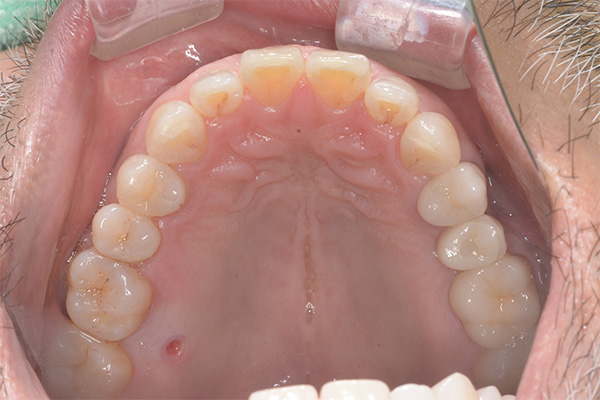

Case.01

インプラントの症例 インプラントの症例

患者様の要望乳歯が残っているので抜いてインプラント

治療を受けたい。

治療期間8ヶ月

治療費用588,500円

治療内容右上3番にインプラント埋入

治療のリスクネジが緩む可能性あり